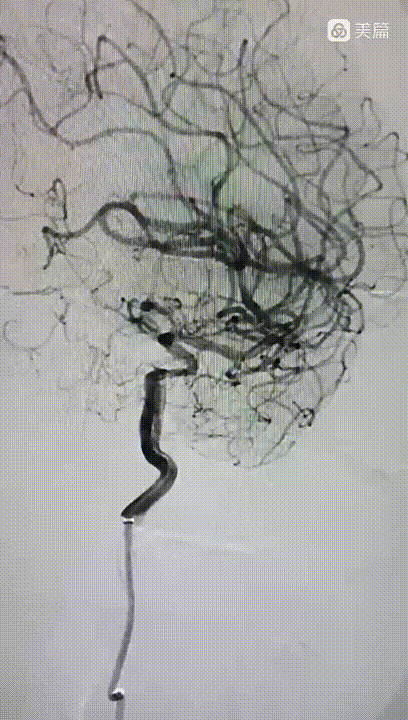

造影显示:左侧颈内动脉C1段呈火苗样窜动,提示:远端闭塞可能。说明病情在持续加重,血栓堆积闭塞了血管。

颈内动脉C1~C3血管迂曲呈u型、S型改变。血液滞留。

再次清理防止碎栓逃逸:抽吸至血流通畅,造影显示血管再通。但极重度狭窄。一抽见真情。